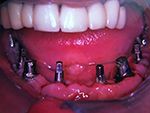

Die folgenden Patientenfälle sollen Ihnen einen Einblick in die Möglichkeiten der modernen Implantation geben.

Komplett-Implantation: